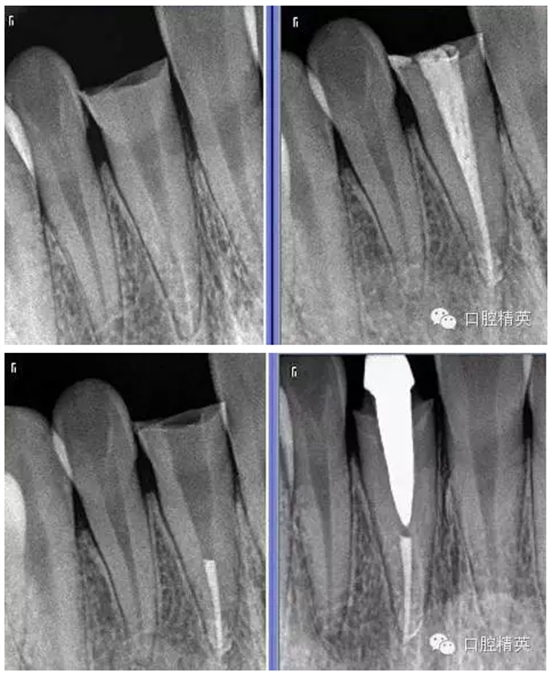

6:術前后的X-RAY。

術前 ↑

術后 ↓